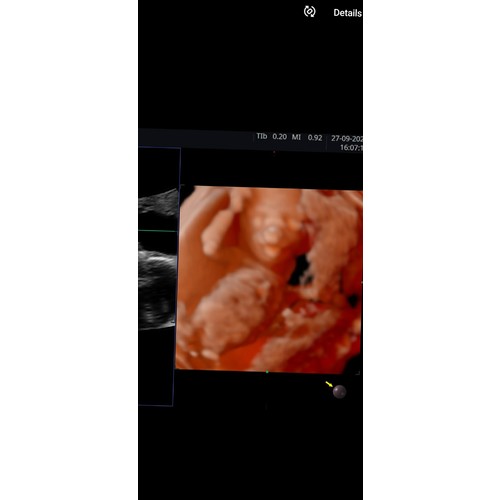

Ons meisje had geen zin in 3d foto’s van haar gezichtje en liet liever zien hoe lenig ze is 🤪